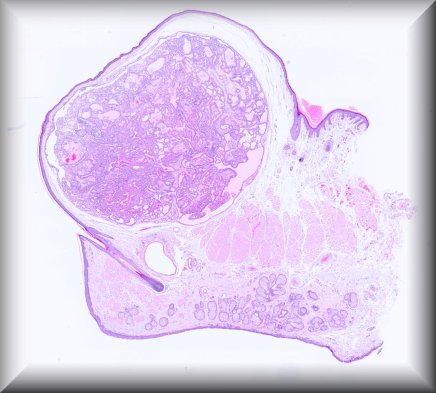

Dietmar Thal (Leuven): Eyeball resection for melanoma in an 83-year old male Alzheimer's disease patient |